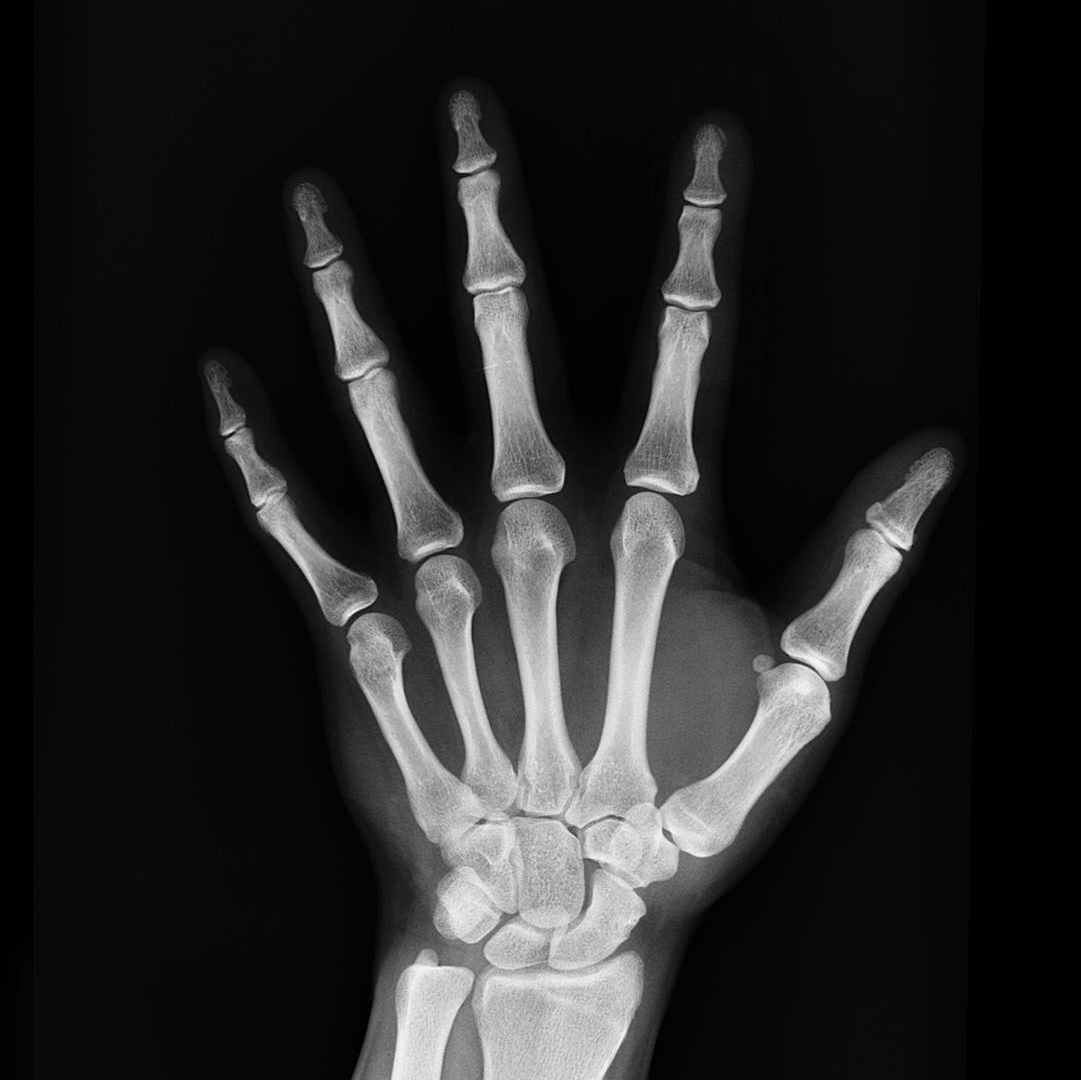

The skeletal system provides us with five very important functions:

I think you would agree the all five of the above are crucial to maintaining good health. Nutrition and exercise play a vital role in the health of your skeletal system. For example, what pregnant mothers eat while carrying their child in the womb will affect the eventual bone mass of that child as an adult. The bad news is that all of us will begin to see decreases in our bone mineral density once we reach about 30 years old. Not intervening on this process can lead to osteoporosis.

Osteoporosis is sometimes known as the “silent thief” because it proceeds without symptoms. Osteoporosis causes bones to weaken and weak bones can result in fractures. Older adults and women going through menopause are especially susceptible to developing fractures. The prevention of fractures amongst the elderly is of paramount importance because if they do, their chance of dying shortly afterwards skyrockets.

Anyway, enough of the negative, because there are strategies you can employ to help slow down bone loss and even strengthen your bones. Nutrition and exercise are two teammates that you have in this battle. The well-nourished body will have the ability to repair any tiny cracks or damage itself – old bone out, new bone in. However, in poorly nourished people small problems can proliferate into big ones by further weakening the structures. Regular exercise also plays a key role in the health of your bones. The stress that exercise places on bones challenges them to adapt and increase bone formation – all good things that you want happening.